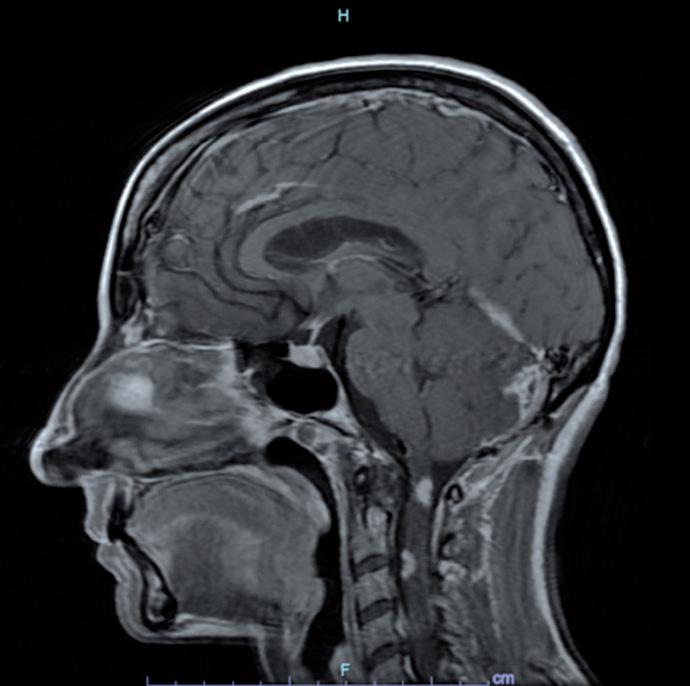

La paziente ha pertanto avviato una seconda linea di trattamento con T-DXd, ottenendo una progressiva riduzione delle lesioni meningee note ai successivi controlli mediante RM, fino ad arrivare a una situazione di stabilità che si mantiene tuttora a 24 mesi dall’avvio del trattamento (figura 1).

Figura 1. Immagini RM prima dell’avvio del trattamento e dopo 6 mesi.